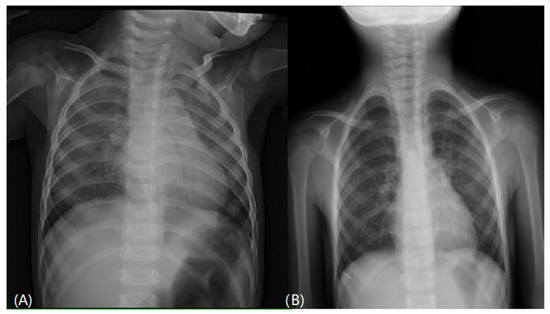

A series of examinations was performed to establish the final diagnosis. Her blood gas pH value was within the normal range, without carbon dioxide retention or metabolic acidosis. A chest x-ray showed diffusely increased density of both lungs (Figure 1A). Lung echo suggested pulmonary edema (Figure 2), and furosemide was administered. Chest

Figure 1. (A) Chest x-ray on admission showed diffuse increased interstitial density of both lungs. (B) Chest x-ray after treatment revealed no radiologic evidence of active cardiopulmonary disease.

After establishing the final diagnosis of SP-C deficiency, we started the treatment with hydroxychloroquine (10 mg/kg/day in two divided doses). We discontinued azithromycin, and gradually tapered down steroid dosage within one month. She was then regularly followed up with through the outpatient department. After two months of treatment with hydroxychloroquine, her condition had markedly improved and her oxygen demand decreased gradually. Follow-up echocardiography was normal, without pulmonary hypertension; therefore, we discontinued sildenafil use. She took hydroxychloroquine for 21 months, and room air was well tolerated without cyanosis or exertional dyspnea. A chest X-ray revealed normal findings (Figure 1B), although lung function tests performed after halting medication still showed restrictive pulmonary disease. She was well fed after respiration improved. Her height (28th percentile) and weight (41st percentile) also caught up to the normal range. Two years after withdrawing the medication, the patient was four years old and she remained well, with no clinical or radiological signs of relapse.